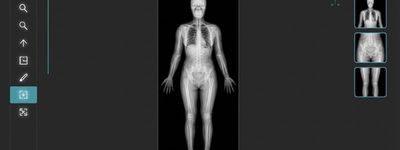

Full Body X-Ray: Benefits and What to Expect

2/16/2026